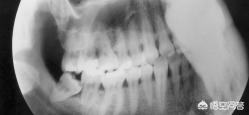

1. 阻生齿,尤其是十几二十岁的年轻人,出现反复头痛可以拍一个牙片,像这样,最后一颗牙齿横着长得,这种很容易反复发炎,引起剧烈牙疼、头痛。这种可以根治,把阻生齿拔掉,注意口腔卫生即可。